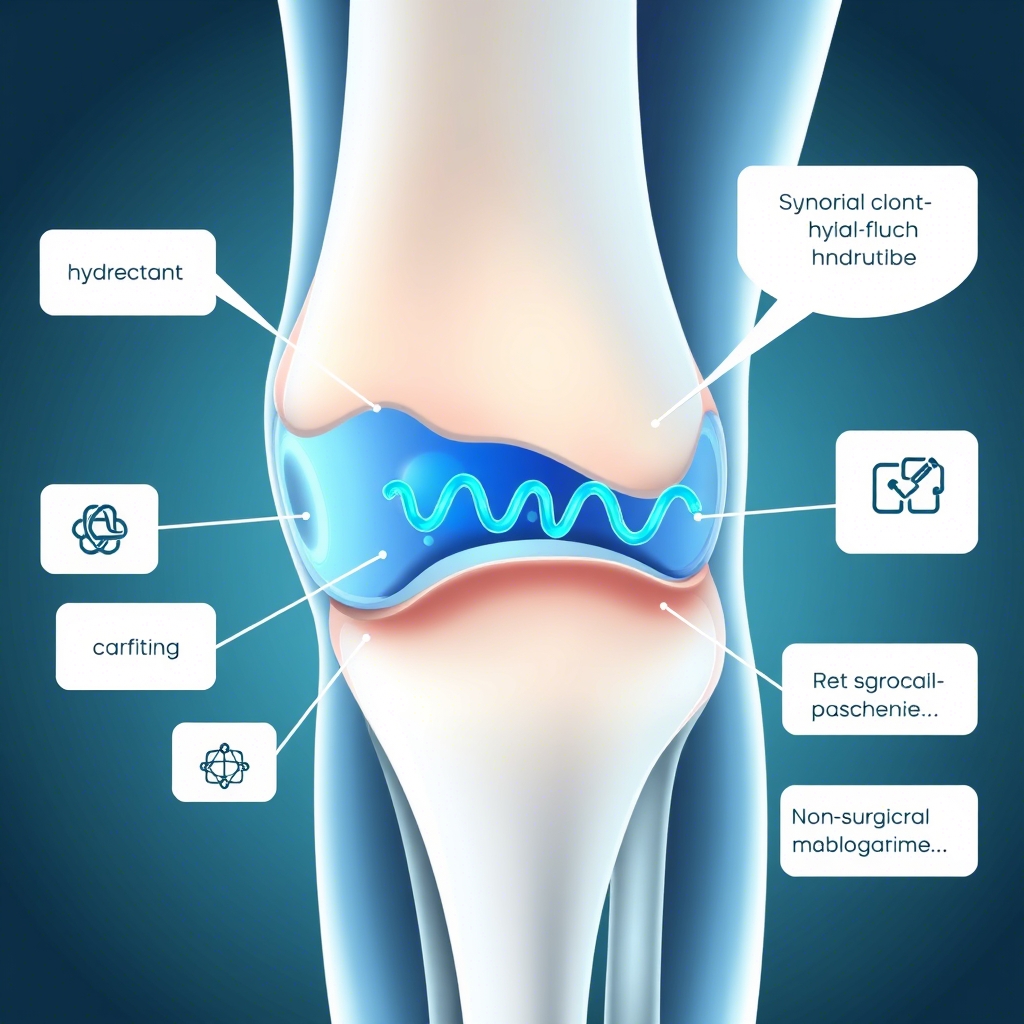

L'acido ialuronico, noto anche come ialuronano, è un importante componente presente in diversi tessuti del nostro organismo. Si tratta di un glicosaminoglicano anionico non solforato con una diffusa distribuzione nei tessuti connettivi, epiteliali e nervosi. La sua struttura molecolare è composta da unità ripetitive di acido glucuronico e N-acetilglucosamina, che conferiscono a questa sostanza proprietà uniche e fondamentali per diverse funzioni biologiche.

Tra le sue principali caratteristiche, l'acido ialuronico si distingue per la capacità di legare e trattenere grandi quantità di acqua, contribuendo così all'idratazione e all'elasticità della pelle e dei tessuti. Inoltre, svolge un ruolo importante nella lubrificazione delle articolazioni, garantendo la corretta mobilità e proteggendo le superfici articolari dall'usura.